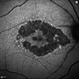

- Optos photograph of a 61-year-old male with a macula on retinal detachment and large horseshoe tear. Patient had no visual changes.